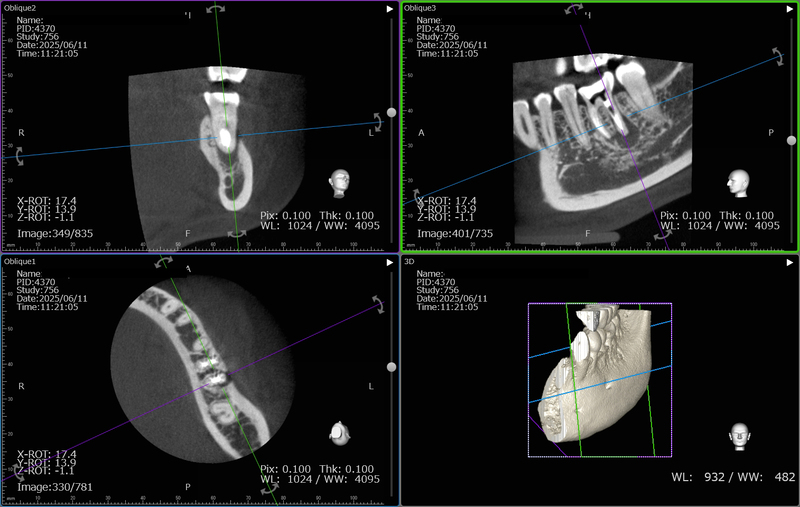

術前のCTになります。歯根の周囲が黒く抜けており、膿が溜まっております。

術後のCTです。黒い部分が小さくなってきており、骨が再生されてきているのが確認できます。